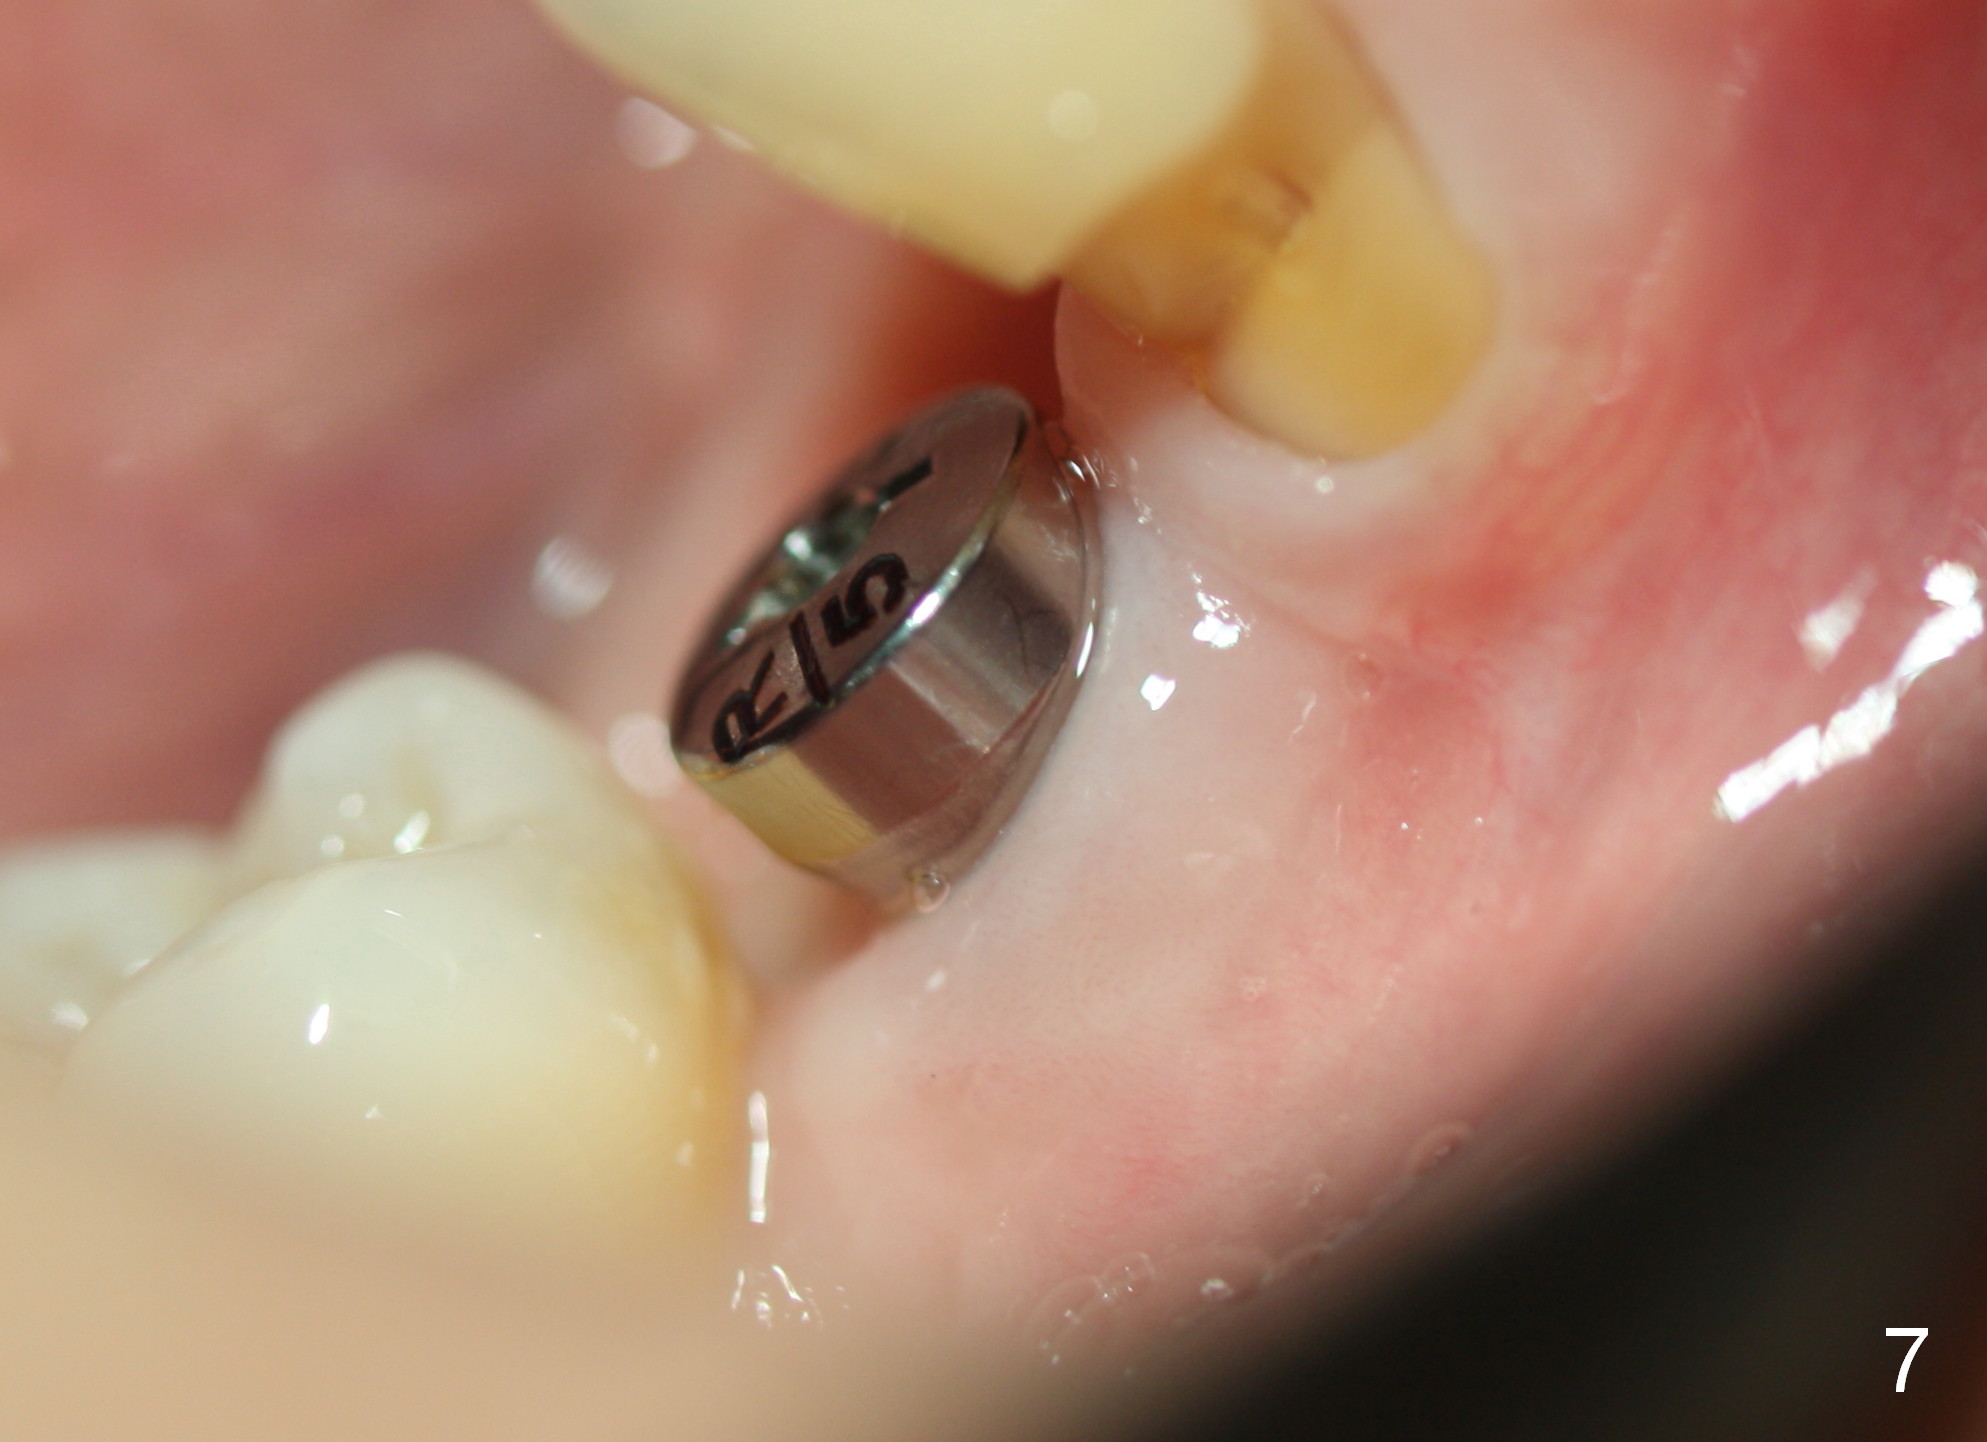

The patient returns less than 2 months postop. The bone sectioned areas are blurring (healing) (Fig.6). The soft tissue is healthy around the healing abutment (Fig.7).